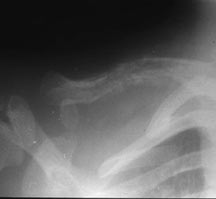

Sites:

- Flat Bones (most common—70%)

- Skull

- Pelvis